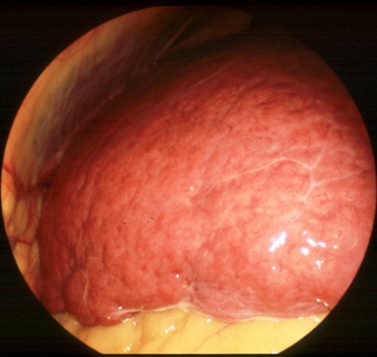

C型慢性肝炎とはC型肝炎ウイルスの感染が原因でおこる疾患です。C型肝炎ウイルスの感染からおおむね30年程度で徐々に慢性肝炎から肝硬変へと進行していきます。下の写真はおなかの中にいれたカメラ(腹腔鏡)で肝硬変に進行していく様子を見たものです。肝硬変になると表面がでこぼこになる様子が分かります。肝硬変になっても よほど進行しないと自覚症状はでませんが、年間約8%の確率で肝臓がんが発生しますので十分な注意が必要です。